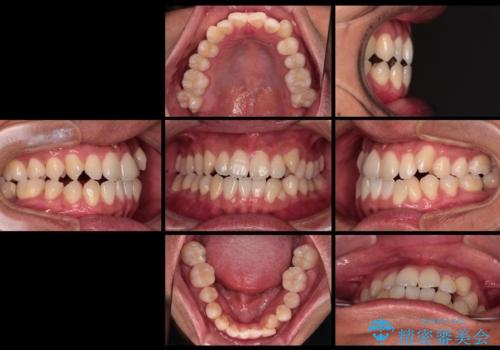

- 上下前歯部のデコボコを主訴として来院された患者様です。

上顎の歯列弓が下顎に対して狭いため、臼歯のかみ合わせがが咬頭対咬頭の状態です。

歯列弓の拡大により約1年で矯正治療を終えることができました。

正中も合わせることができ、非常にきれいに仕上がりました。